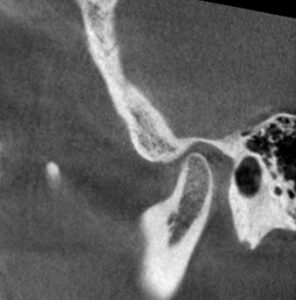

この状態になった時のこの患者さんのCTスキャンの比較はこちらです。

治療前 左側

治療後 左側

治療前 右側

治療後 右側

関節圧迫が取れているのがわかるでしょうか?

これが治療後の状態です。